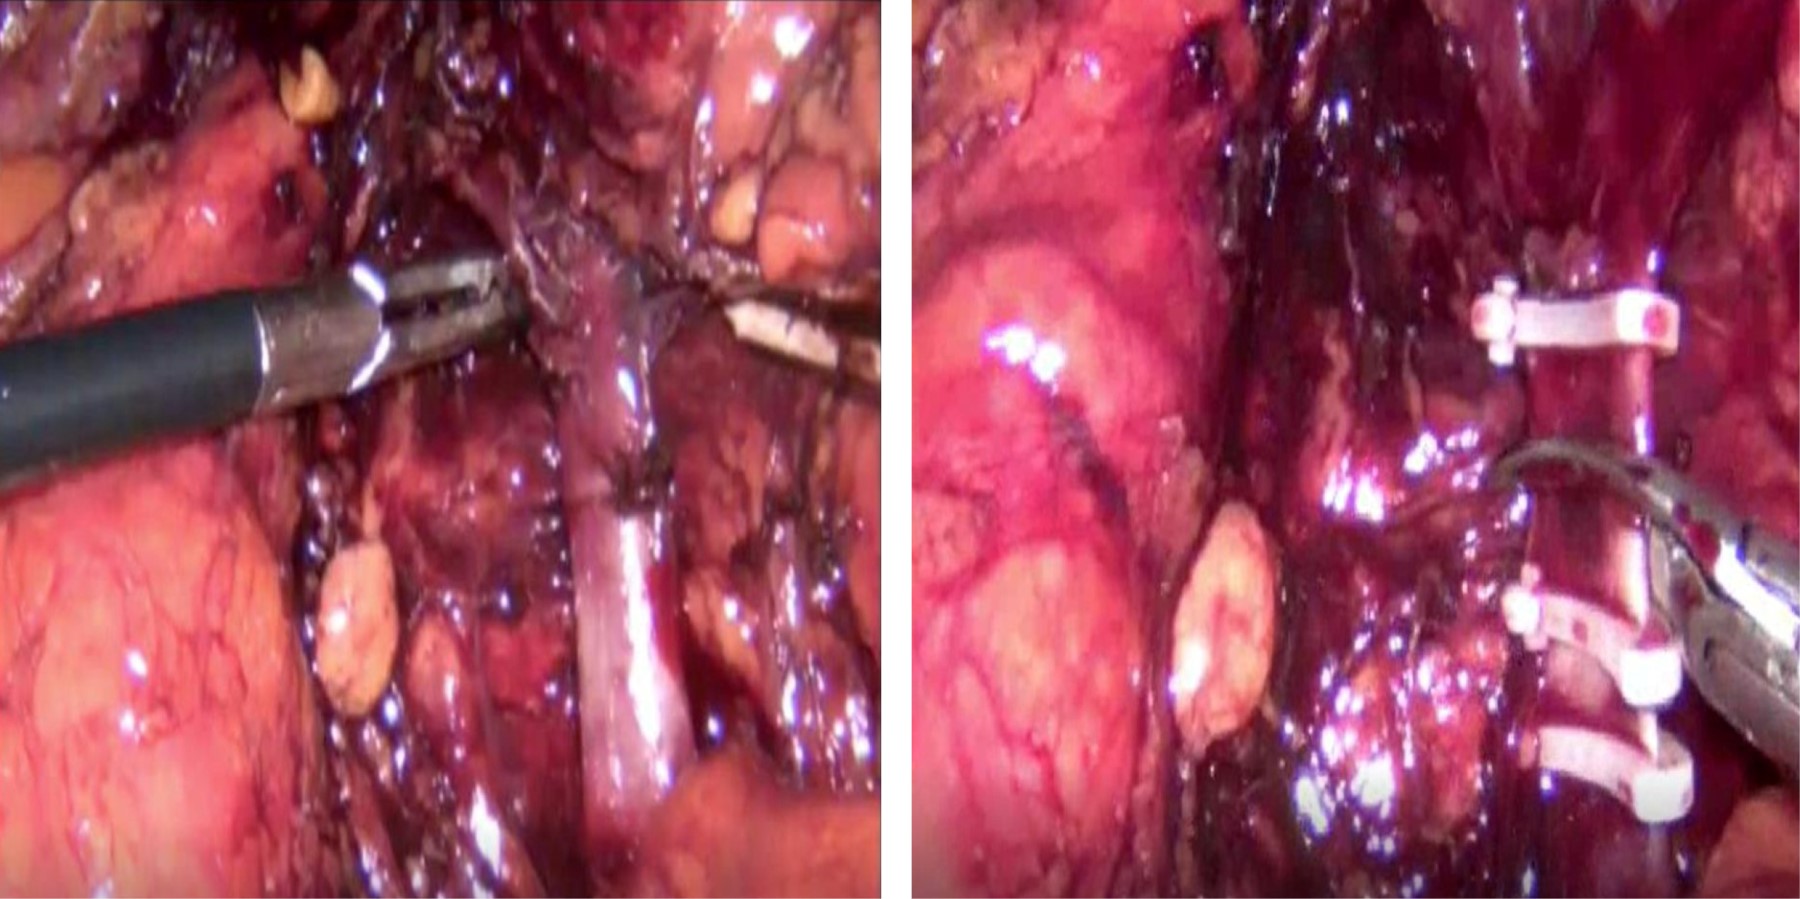

Figure 1

Figure 2

Figure 3

Figure 4

Figure 5